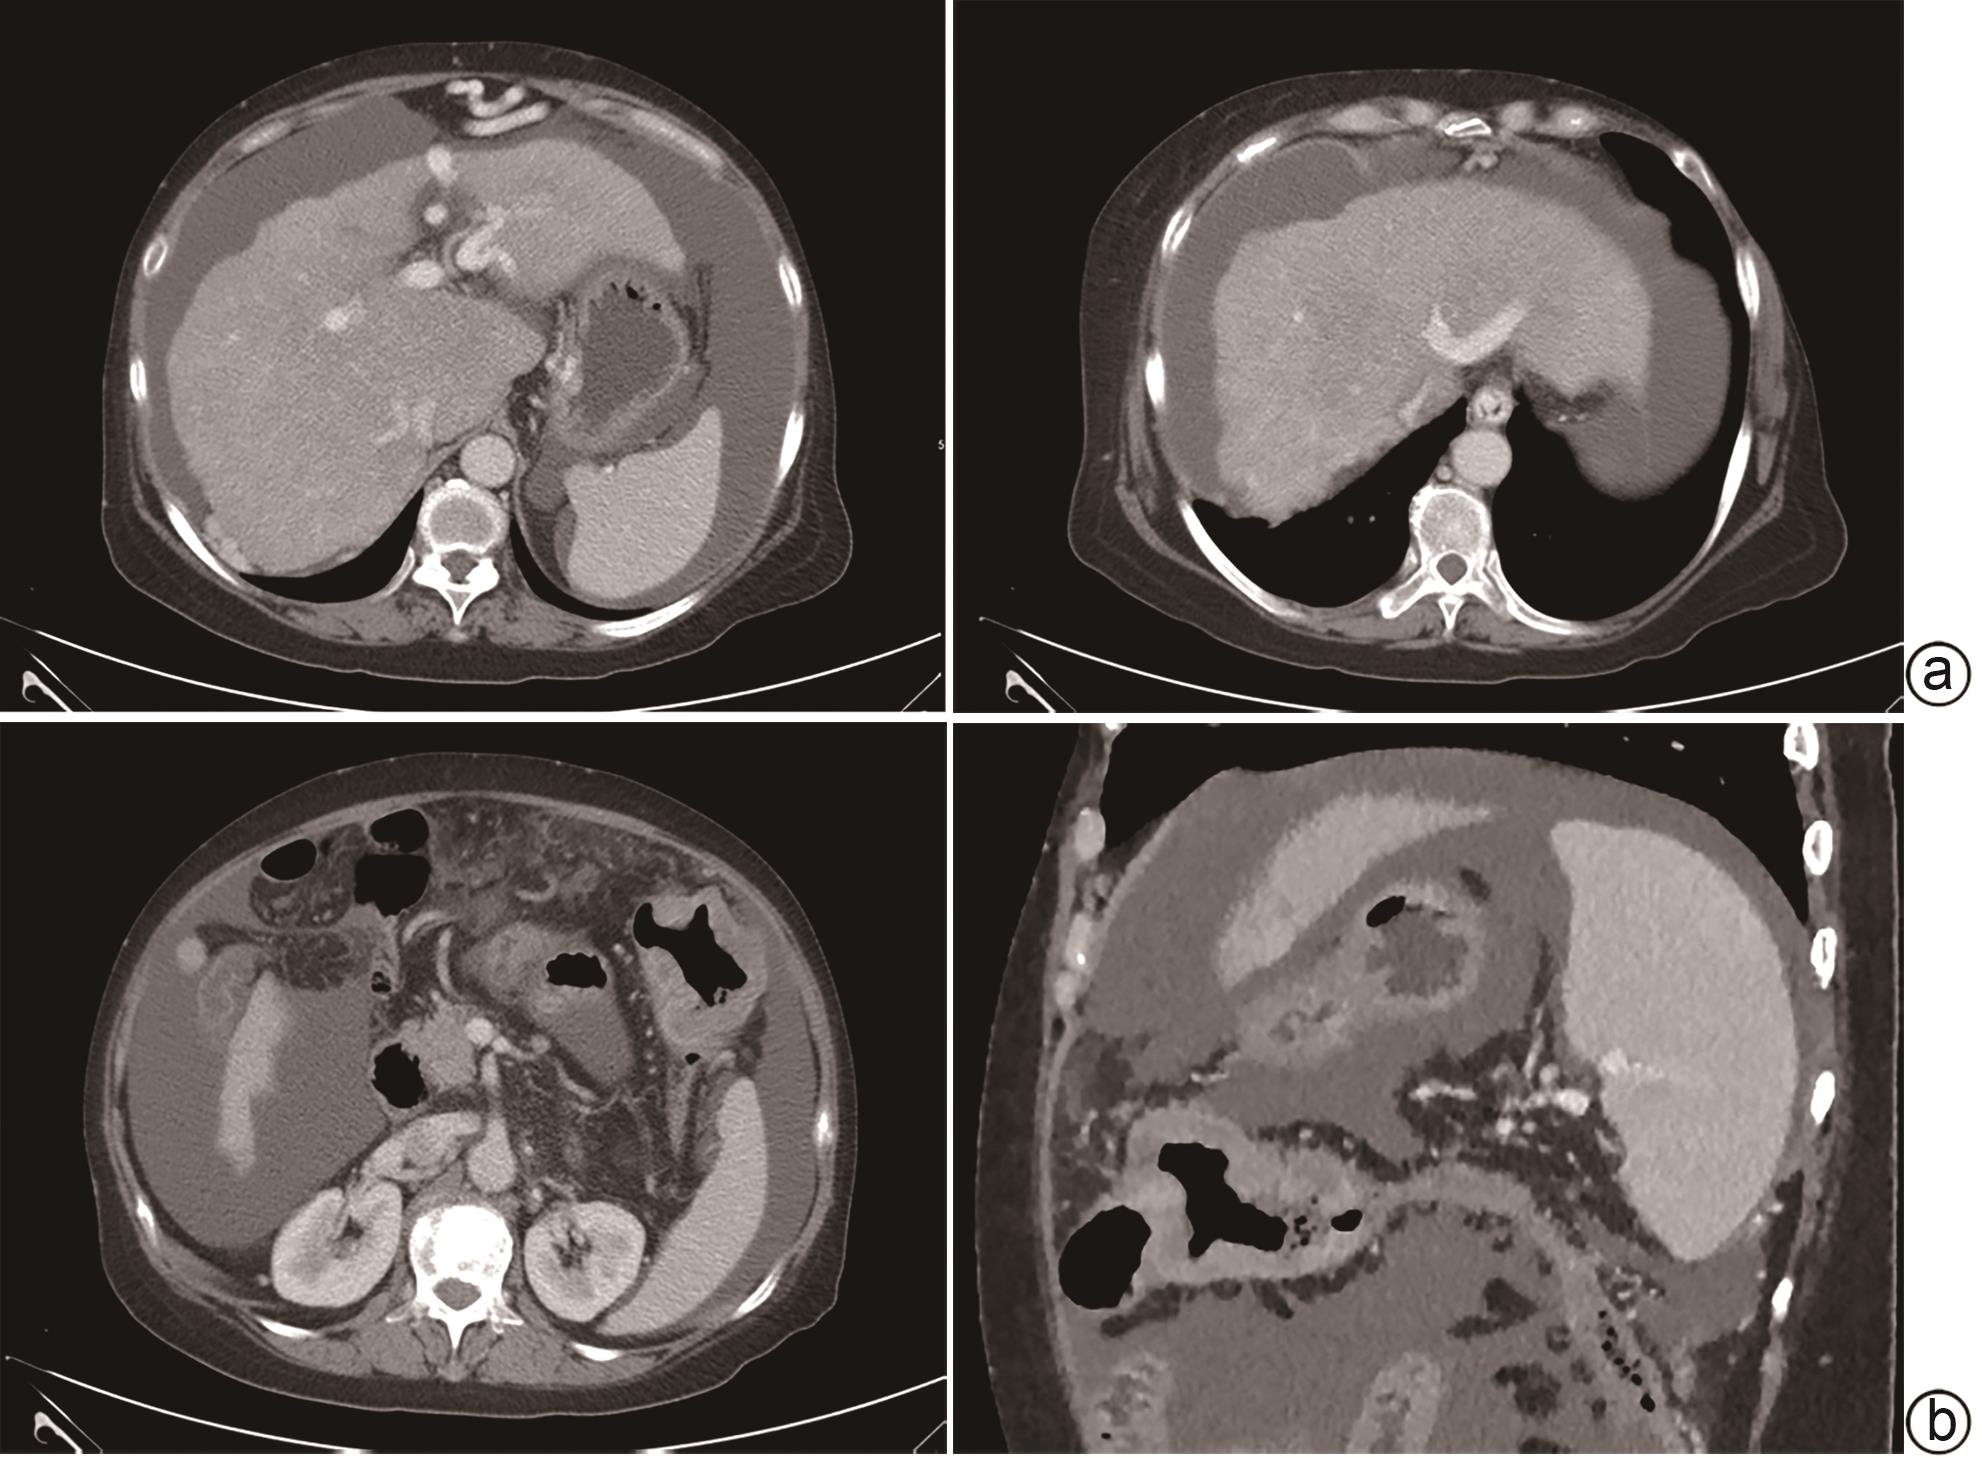

Diagnosis and treatment of decompensated cirrhosis with multiple primary cancers: A case report

Wenting CHAO, Rui HUANG

2024, 40(9): 1868-1872. DOI: 10.12449/JCH240923

Abstract(950) HTML (403) PDF (1776KB)(113)

Abstract:

Multiple primary cancers (MPC) refer to the presence of more than one type of cancer with different histological features and sites in the same individual, and it is relatively rare in clinical practice. This article reports a case of decompensated cirrhosis with MPC and discusses the diagnosis, treatment, and clinical implications of this patient with decompensated cirrhosis and MPC.